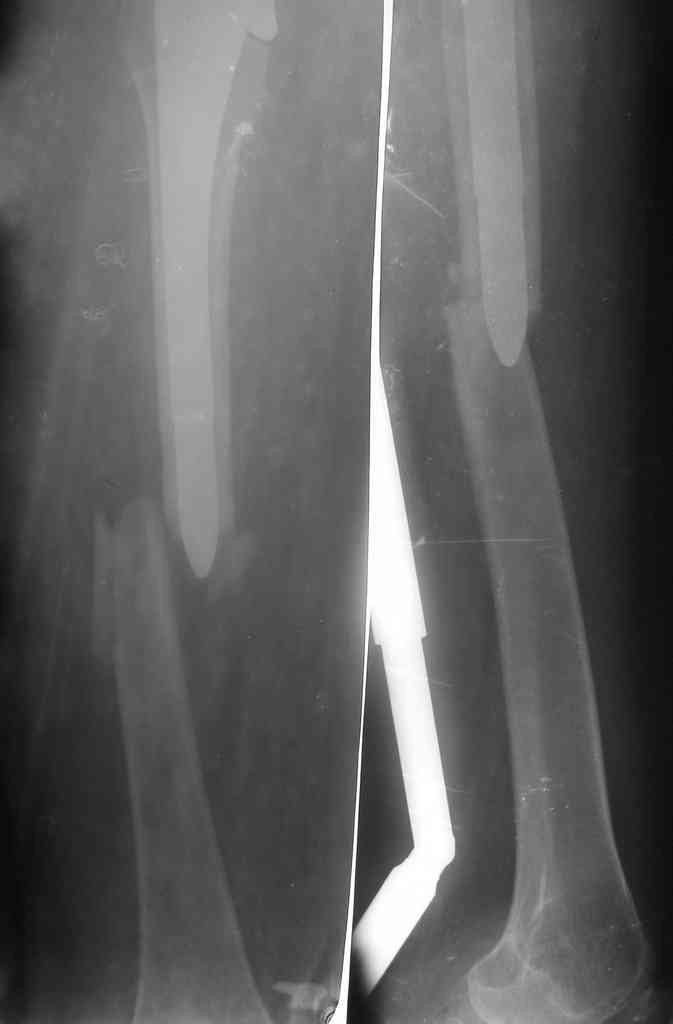

The bridging plate is a weak constuct for angular stresses and hence the deformity. The best option would be a revision THR with an open mind. After exposure one should see the integrity of the cup which is not clearly visible here. The stem is in Valgus and hence the fracture. IT needs to be revised to a long stem like the Wagner system with its 8 fins or a Proximal fit modular stem from J& J. ( both uncemented) Once again plating is not a good option against bending stresses in the femur.

This depends on the stem fixation. If the stem is fixed then it's a Vancouver type B1 fracture and should be fixed with a plate well past the Fx and at least 2-3 shaft diameters above the Fx site proximally (fixed with cerclage wires proximally).

If the stem is loose (Vancouver B2), then it needs to be revised to a longer prosthesis.

I'd remove that bridging plate device and just use a long locking plate with autologous bone grafting. Cortical strut grafts are not necessary, as it looks like the plate has failed, not the bone.

redo fixation is my choice as well, but, I do not use this plate and would not use it again. try

Locking plate with cables proximally, plus screws and screws distally.

By the way, the Mennen type plate with clamp like architecture is given up & no more used for the periprosthetic #s.

according to the Vancouver classification thi looks like a B1 type so ORIF is indicated.

This kind of plate is "forbidden" in literature because has bad results with failure at 1 or 2 months.

The correct ORIF is with a LCP system with a good fixation either proximally or distally (longer than this one).